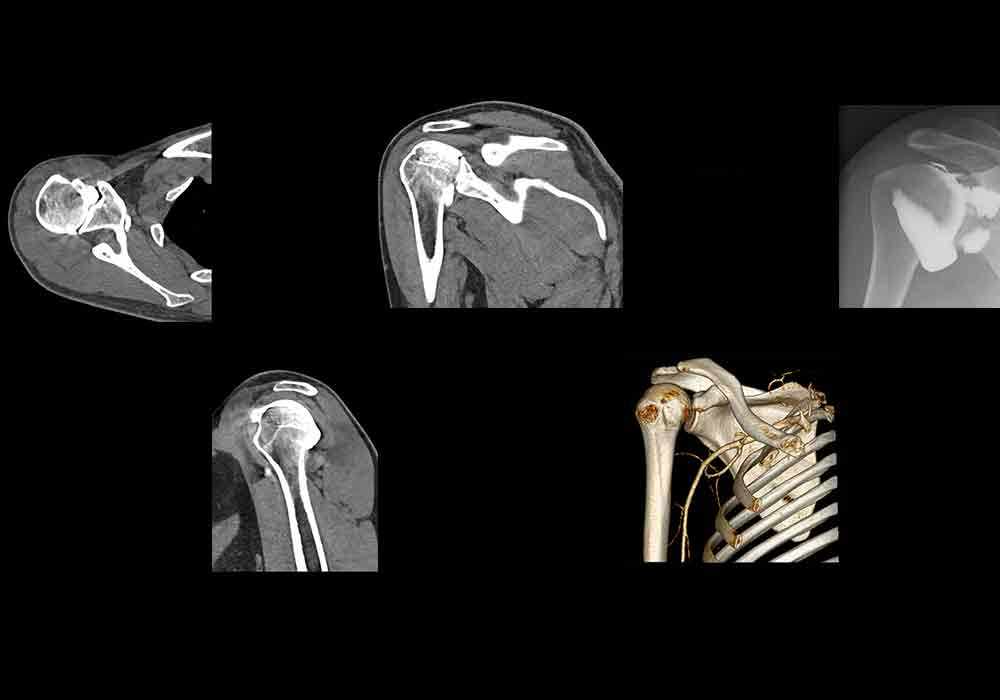

肩(CT关节造影)

- Antoine MICHEAU, MD , Denis HOA, MD

- 发布日期: 2016年5月20日 | 最新更新 2025年3月18日